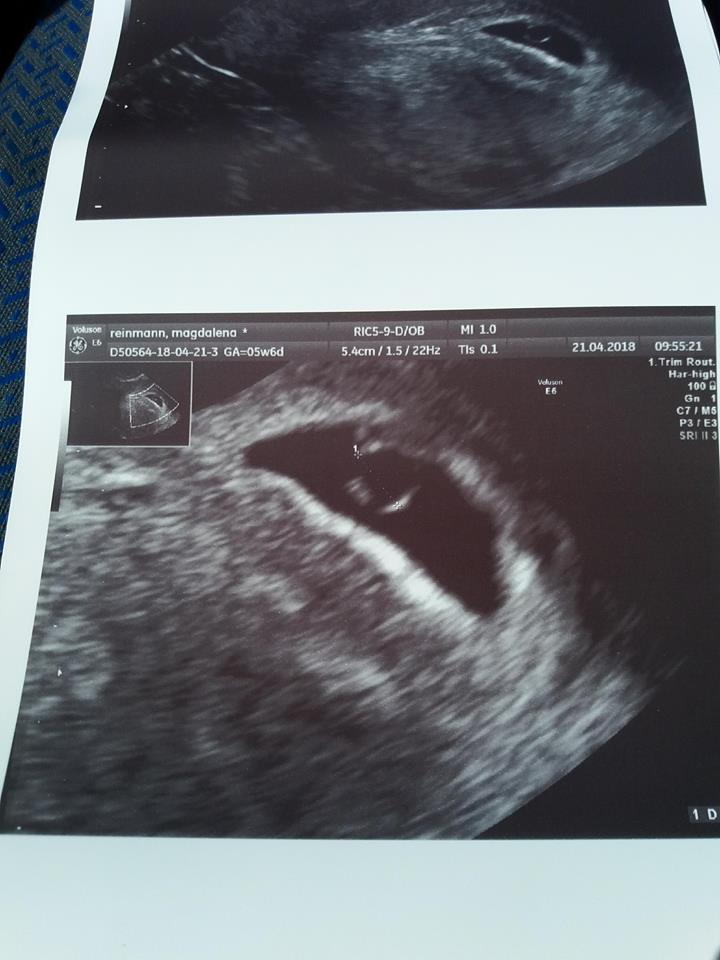

A jakie miałaś ostatnio parametry pęcherzyka i zarodka? Tzn chodzi mi o wielkości.dziś 6tc2d

Gdzie tu pisze na zdj ile dzidzius ma?![]()

To jest raczej nie możliwe żeby w 7 tygodniu miało 3mm moje w 6 miało 4 mm A w 8 ma 1.5 cm

Nie stresujcie jej. Na zdjeciu jest napisane 7t1d wg terminu miesiaczki, ale jesli ma termin na 10 grudnia to ciaza mozliwe, ze jest mlodsza ok tydzien i moze miec 3 mm. Podejrzewam, ze z usg wyszloby ok 6t0d, ale nie jest to napisane na zdjeciu. Wiec moim zdaniem jak najbardziej moze miec zarodek 3 mm. Serce bije, a to najwazniejsze. Nie porownujcie swoich ciaz, bo kazda jest inna.To jest raczej nie możliwe żeby w 7 tygodniu miało 3mm moje w 6 miało 4 mm A w 8 ma 1.5 cm

Pęcherzyk był 7,5 cm, a zarodek ok 1mm.A jakie miałaś ostatnio parametry pęcherzyka i zarodka? Tzn chodzi mi o wielkości.